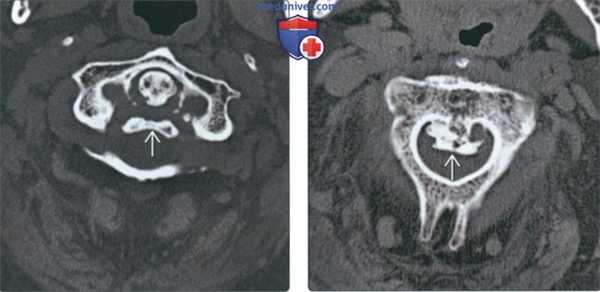

(Слева) На аксиальной КТ без КУ у пациента с ДИСГ визуализируется крупный вентральный остеофит с кортикальной пластинкой, оказывающий воздействие на гортаноглотку. При существенном воздействии возможно появление симптоматики.

(Справа) На аксиальной КТ определяется массивная оссификация со смещением левой сонной артерии и воздействием на гортаноглотку слева. Расщелина в оссификате на уровне межпозвонкового диска - частая находка. Возможна сопутствующая дисфагия, обусловленная не только механической обструкцией пищевода, но и воспалением и фиброзом.